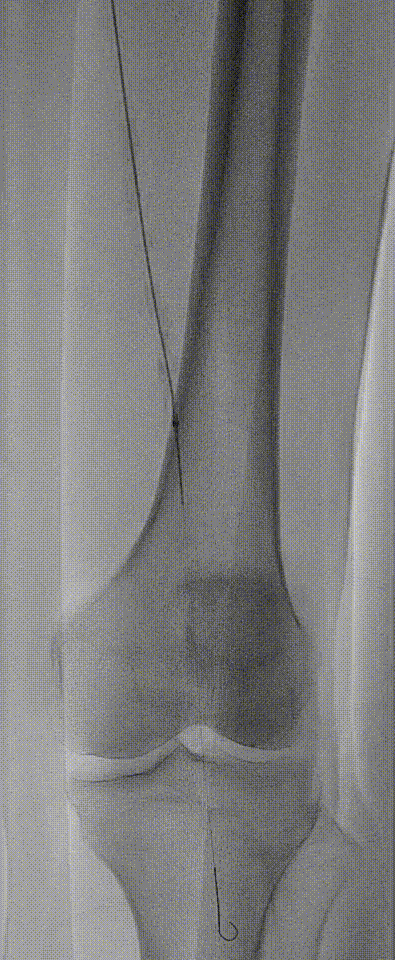

图:OA 基线造影

图:IVUS测量

图:Diamondback 360 减容

图:DCB扩张后 全程造影